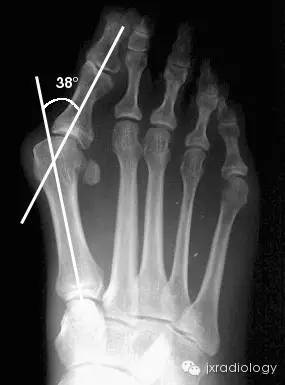

△ 常用测量角

常用测量角:

1、跖间角 (Intermetatarsal Angle, IMA) value币,第1、2跖骨纵轴延长线之夹角,正常6°~11°,正常 < 9°;

2、踇外翻角(Hallux Valgus Angle,HVA;又称 Hallux abductus angle,HAA)第1跖骨纵轴线与第1趾近节趾骨纵轴线之夹角,正常 < 20°value币。

踇外翻分度:

根据跖间角 (IMA)踇外翻角(HAA)的大小将其分为:

轻度(HAA:15°~30°;IMA≤13°);

中度(HAA:30°~40°;IMA:13°~16°);

重度(HAA≥40°;IMA≥16°)value币。